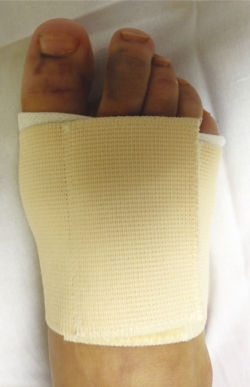

A los 10 días, se retira el vendaje posquirúrgico y se coloca una banda metatarsal que tiene un velcro que permite apretar o aflojar según el edema del pie (Figura 6). Esta faja metatarsal proporciona estabilidad a la artrodesis y el paciente es autorizado a realizar carga completa con el zapato ortopédico y la faja hasta las 5 semanas.

figura-6.jpg

Figura 6. Faja estabilizadora para antepié utilizada en el postoperatorio de la intervención de artrodesis. También es utilizada en postoperatorio de cirugía del hallux valgus.